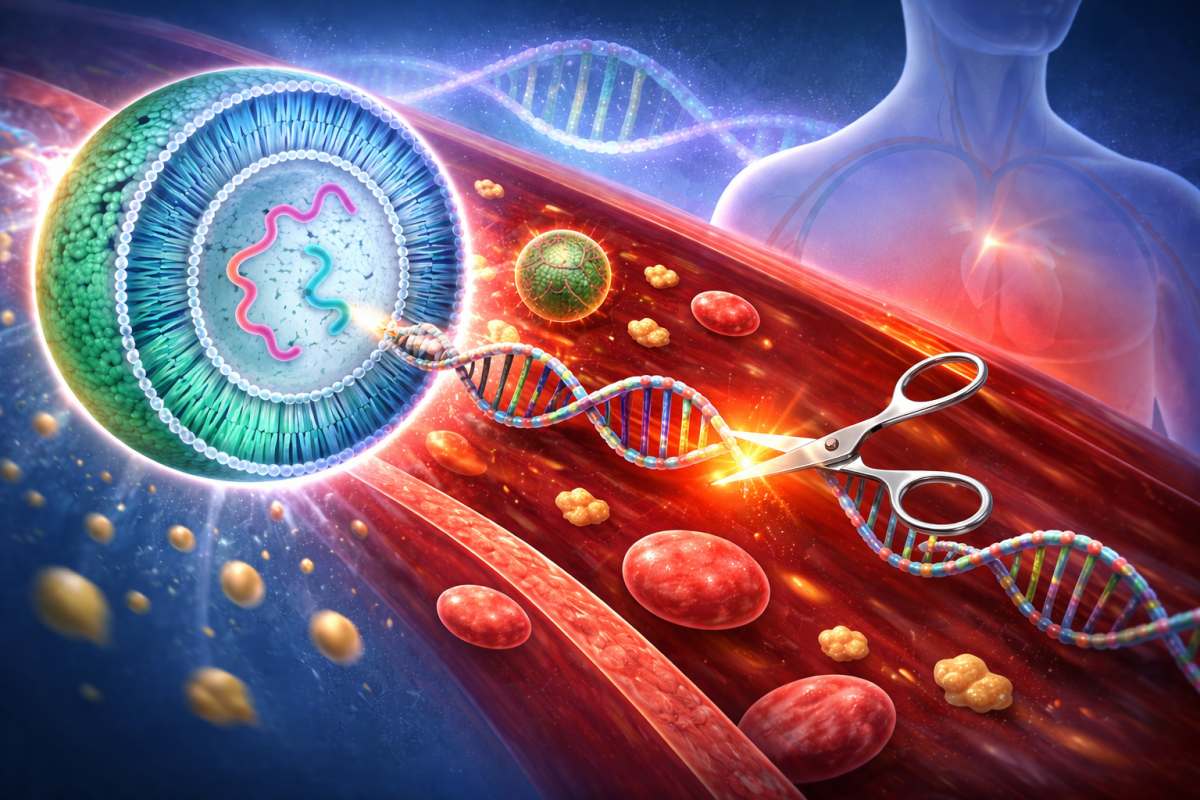

A Genetic Fix for a Genetic Crisis

One infusion of gene therapy could end the daily statin regimen that keeps millions alive, and change how we think about treating chronic disease.